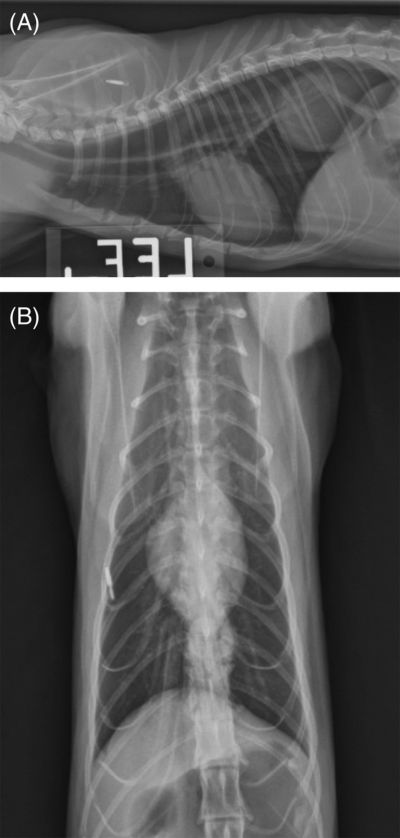

Les auteurs de ces travaux alertent également sur les nombreux cas où une radiographie simple du thorax ne permet pas de déceler la hernie, en particulier si elle est intermittente (voir les radiographies en exemple).